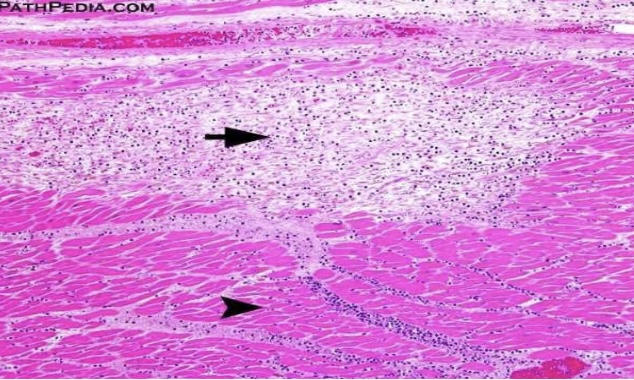

Zenker’s necrosis